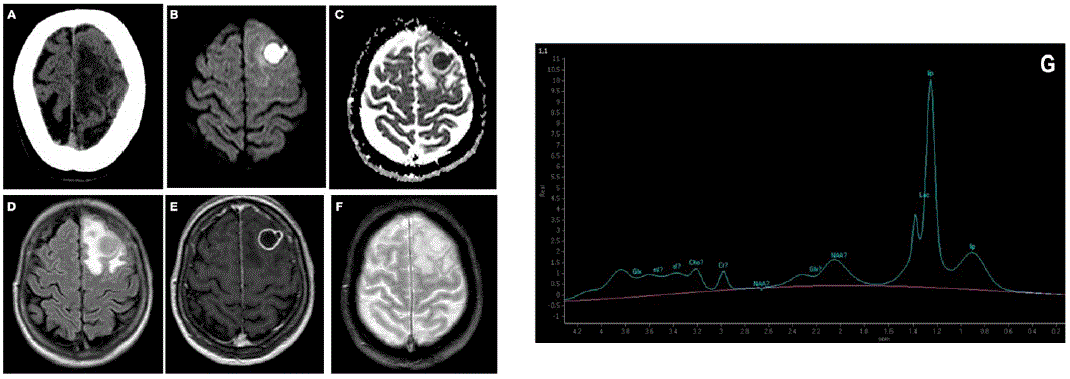

She had leukocytosis (12.3x109 cells/L), lymphopenia (370 cells/mL) and a D-dimer value above the detection limit (>10,000 ng/dL). Inflammatory markers (sedimentation rate and procalcitonin) and serum complement levels were normal. A head CT scan was carried out and showed a cystic lesion in the left frontal lobe with associated edema (Figure 1A). A brain MRI was performed. The T1-weighted, T2-weighted and FLAIR sequences showed a sharply defined lesion (16.8 x 16 x 15.1 mm) in the left frontal lobe, with a large area of perilesional edema (Figure 1D). Diffusion weighted imaging showed elevated molecular restriction of the content with reduced apparent diffusion coefficient (Figure 1B,C). The lesion showed an enhancing rim after applying IV contrast (Figure 1E). There were no hemorrhage or calcium components in the susceptibility weighted imaging sequence (Figure 1F). Magnetic resonance spectroscopy demonstrated normal creatinine, choline and N-acetyl aspartate levels with a markedly elevated lactic acid and lipids peak (Figure 1G).

Panel A shows the head CT scan, which reveals a cystic lesion with associated edema in the left frontal lobe found. Panels B-F: Findings on brain MRI. Panel B and C: diffusion weighted imaging, which demonstrates an elevated molecular restriction of the content of the lesion with reduced apparent diffusion coefficient. Panel D: FLAIR sequence, which shows a sharply defined lesion in the left frontal lobe and corroborates the presences of a large area of perilesional edema. Panel E shows the lesion’s enhancing rim after applying IV contrast in T1Weighted imaging. Panel F shows the susceptibility weighted imaging sequence, which reveals no sings of hemorrhage or calcium components. Panel G shows the magnetic resonance spectroscopy. The study reveals normal creatinine, choline and N-acetyl aspartate levels with a markedly elevated lactic acid and lipids peak.

Figure 1 Head CT scan and brain magnetic resonance imaging and magnetic resonance spectroscopy

Nowadays, MRI and CT scans are important tools for the diagnosis of brain abscess and for ruling out alternate diagnosis, with Nocardial brain abscesses normally presenting as hyperenhanced multiloculated ring lesions with the variable presence of perilesional edema.4 The more indolent clinical picture presented in Nocardial cerebral abscesses in immunocompetent patients make the full utilization of these studies even more vital in the differential diagnosis, as immunocompetent patients the lesions may resemble infarcts or tumors.4 Magnetic resonance spectrum is an useful resource for distinguishing brain abscess from other lesions (gliomas, and cystic or necrotic foci).4 This is due to the fact that brain abscess have scarce amounts the metabolites normally found in healthy brain tissue (N-acetyl aspartate, creatine, and choline) and have elevated levels of lactic acid. Other helpful MRI modality is diffusion weighted imaging, which shows an hyperintense signal inside the abscess cavity with a low apparent diffusion coefficient (ADC).4 Both MRI findings were present in our patient and helped to define the diagnosis within the first 24 hours and thus provide prompt treatment.